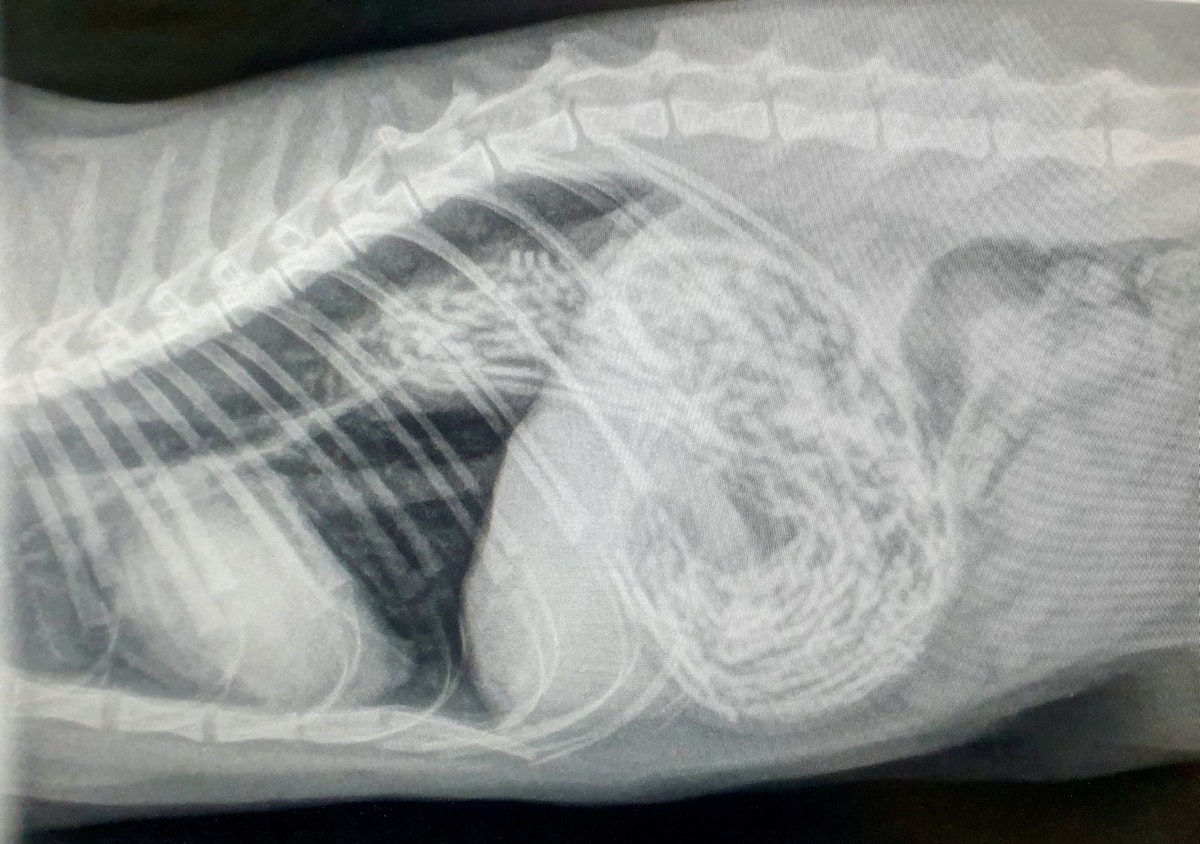

• 1 /6 Kater "Berry" verschluckte beinahe 50 Haarbänder.

• 2 /6 Die Notoperation musste schnellstmöglich durchgeführt werden.

• 3 /6 So sehen 50 unverdaute Haarbänder aus.